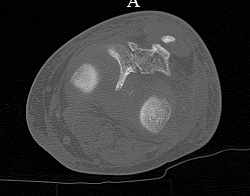

[Ortho] перелом проксимальной тибии + вывих бедра

Серия КТ сканов в аппарате